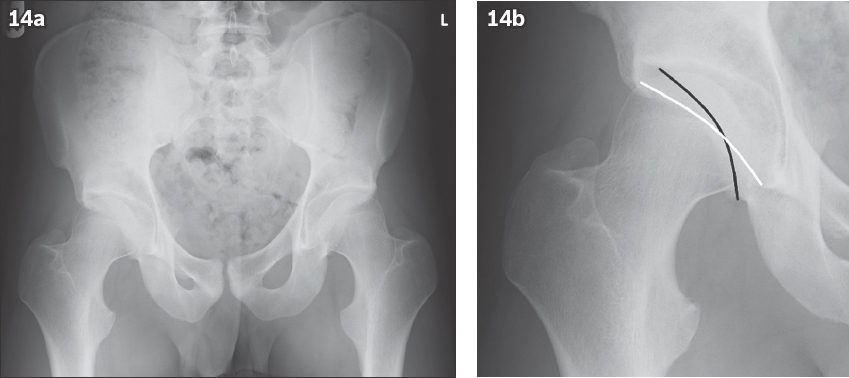

Fig. 14

(a & b) Pelvic radiographs show an example of bilateral acetabular retroversion. The crossover sign is seen in (b), where the posterior wall (black line) of the acetabulum is seen to cross over and project medial to the anterior wall (white line) of the acetabulum.